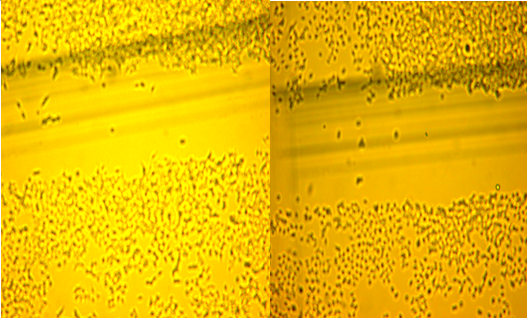

酶法小分子果胶处理正常细胞 碱法小分子果胶处理正常细胞

MDA-MB-231细胞在Transwell小室侵袭情况比较,下面三幅图可以看出,对照组侵袭程度较高,FU加改性果胶组侵袭程度要比FU组和对照组低。